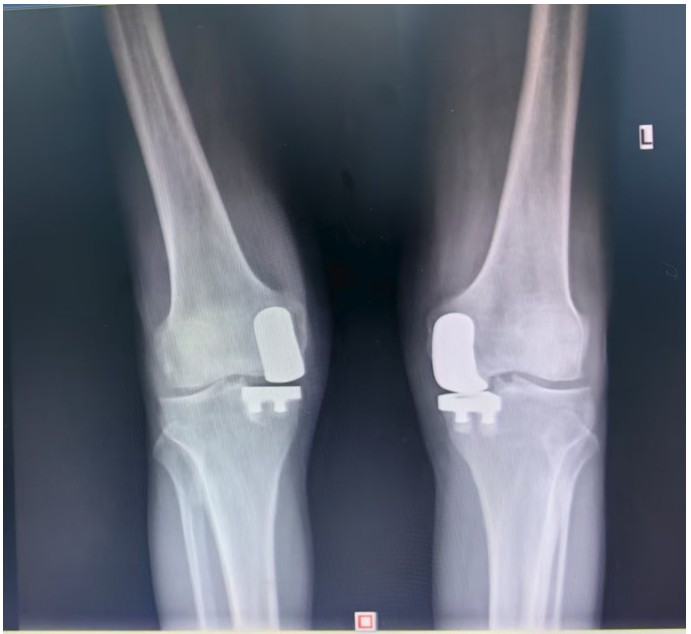

通訊員王珂報(bào)道:近日,一位來(lái)自江西的大爺跨越六百公里,專程來(lái)到衡陽(yáng)市中心醫(yī)院關(guān)節(jié)外科求診。羅湘平主任醫(yī)師、彭健副主任醫(yī)師團(tuán)隊(duì)熱情地接待了患者,并成功為其實(shí)施了“雙側(cè)人工膝關(guān)節(jié)單髁置換術(shù)(UKA)”。術(shù)后膝關(guān)節(jié)功能顯著改善,第二天便可下地活動(dòng),雙側(cè)膝關(guān)節(jié)活動(dòng)度輕松達(dá)到90°,對(duì)手術(shù)效果非常滿意,已于9月10日順利出院。

據(jù)了解,患者1年前無(wú)明顯誘因出現(xiàn)雙膝關(guān)節(jié)疼痛,以右側(cè)膝關(guān)節(jié)為主,近5個(gè)月來(lái)雙膝關(guān)節(jié)疼痛明顯加重,不但日常行走困難,生活質(zhì)量更是受到極大影響。經(jīng)多家醫(yī)院治療效果均不理想,了解到衡陽(yáng)市中心醫(yī)院關(guān)節(jié)外科在關(guān)節(jié)置換領(lǐng)域擁有豐富的臨床經(jīng)驗(yàn)和良好的患者口碑,毅然決定赴衡求醫(yī)。醫(yī)生發(fā)現(xiàn)患者雙膝關(guān)節(jié)已有內(nèi)翻畸形,關(guān)節(jié)內(nèi)側(cè)骨性膨大,X線提示雙膝退行性病變,雙膝內(nèi)側(cè)間隙明顯狹窄,手術(shù)為最佳治療方式。為了達(dá)到根治目的,羅湘平主任醫(yī)師、彭健副主任醫(yī)師為患者進(jìn)行了詳細(xì)查體及綜合評(píng)估,術(shù)前組織開展多學(xué)科討論(MDT)。考慮到易叔叔的膝關(guān)節(jié)骨關(guān)節(jié)炎僅局限于內(nèi)側(cè),外側(cè)間室軟骨良好,若采用全膝關(guān)節(jié)置換術(shù)會(huì)將失去正常關(guān)節(jié)間室的軟骨與韌帶,創(chuàng)傷較大,便為其制定了右膝關(guān)節(jié)單髁置換手術(shù)治療方案。在充分完善術(shù)前準(zhǔn)備后,羅湘平主任、彭健副主任醫(yī)師團(tuán)隊(duì)為患者實(shí)施了右側(cè)膝關(guān)節(jié)單髁置換術(shù)。手術(shù)過(guò)程順利,團(tuán)隊(duì)?wèi)?yīng)用微創(chuàng)術(shù)式(MIS)及“精準(zhǔn)間隙平衡技術(shù)”,最大程度減少了手術(shù)創(chuàng)傷,為術(shù)后快速康復(fù)奠定了堅(jiān)實(shí)基礎(chǔ),術(shù)后第二天即可借助助行器下地活動(dòng)。6天后團(tuán)隊(duì)順利為患者實(shí)施了左側(cè)膝關(guān)節(jié)單髁置換手術(shù)。目前,易叔叔在關(guān)節(jié)外科醫(yī)護(hù)團(tuán)隊(duì)的精心指導(dǎo)和康復(fù)治療下,恢復(fù)情況良好,雙側(cè)膝關(guān)節(jié)活動(dòng)度輕松達(dá)到90°,膝關(guān)節(jié)功能顯著改善,能夠獨(dú)立下地行走,對(duì)手術(shù)效果非常滿意,已于9月10日順利出院。